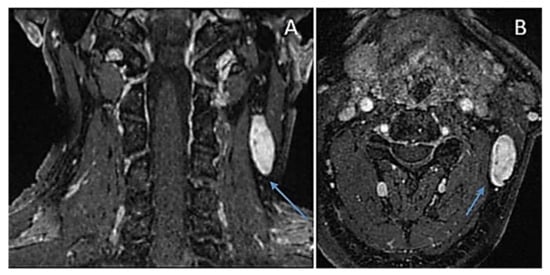

| SMARCB1-related schwannomatosis (SWNTS 1) LZTR1-related schwannomatosis (SWNTS2) [SMARCB1/LZTR1-schwannoma predisposing syndrome (SMARCB1/LZTR1-SPS)] [SWNTS1, MIM # 162091; SWNTS2, MIM # 615670] Chromosome 22q11.23 (SMARCB1 gene); chromosome 22q11.21 (LZTR1 gene): (a) at least one pathologically confirmed schwannoma or hybrid nerve sheath tumour and SMARCB1 or LZTR1 pathogenic variant in an unaffected tissue (e.g., blood); (b) a common SMARCB1 or LZTR1 variant in two anatomically distinct tumours; Main features: multiple non-VIII cranial nerve, non-intradermal, cranial, spinal and peripheral schwannomas (in the absence of NF2 stigmata); SWNTS1 = additional extra-axial, extra-medullary meningiomas and occasionally unilateral VIII nerve schwannomas; SWNTS2 = later onset of disease (up to 60 years), schwannomas affecting various body regions (extremities, spinal cord, chest wall, subcutaneous); |

| MosaicSMARCB1-related schwannomatosis (SWNTS 1) MosaicLZTR1-related schwannomatosis (SWNTS2) [Mosaic SMARCB1/LZTR1-schwannoma predisposing syndrome] (Mosaic SMARCB1/LZTR1-SPS) [Mosaic SWNTS1, MIM # 162091; Mosaic SWNTS2, MIM # 615670] Chromosome 22q11.23 (SMARCB1 gene); chromosome 22q11.21 (LZTR1 gene): (a) at least one pathologically confirmed and SMARCB1 or LZTR1 pathogenic variant in an unaffected tissue (e.g., blood) in < 50% cells analysed; (b) a common SMARCB1 or LZTR1 variant in two anatomically distinct tumours Main features: see the above features of above SWNTS1 and SWNTS2 |